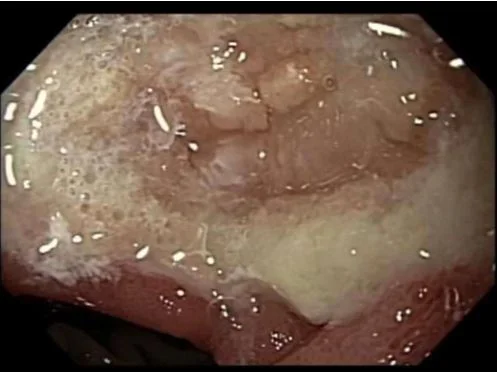

Subsequent endoscopy confirmed large marginal ulcer. Patient discharged on conservative management.

Image from endoscopy shows large ulcer at the GJ anastomosis